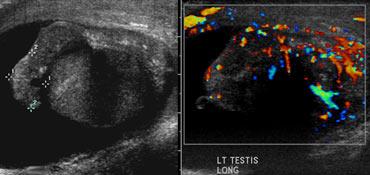

Color doppler

Sự vắng mặt hoàn toàn của dòng chảy máu trong tinh hoàn và dòng chảy máu ngoài tinh hoàn bình thường trên hình ảnh Doppler màu có giá trị chẩn đoán, nếu dòng chảy ở tinh hoàn đối bên bình thường.

Tuy nhiên, sự hiện diện của dòng chảy trong tinh hoàn không loại trừ khả năng xoắn tinh hoàn, vì tắc nghẽn mạch máu không hoàn toàn đôi khi có thể xảy ra hoặc xoắn tinh hoàn ngắt quãng.

Trường hợp bên trái cho thấy xoắn tinh hoàn trái.

Trường hợp này rất rõ ràng vì không có dòng chảy ở bên bị ảnh hưởng, đồng thời cũng có sự khác biệt về độ hồi âm.

Trong trường hợp xoắn kéo dài, tinh hoàn thường giảm âm và không đồng nhất, thường kèm theo tràn dịch màng tinh hoàn xung quanh.

Khi các dấu hiệu siêu âm này xuất hiện, khả năng cứu vãn tinh hoàn bằng phẫu thuật là rất thấp.